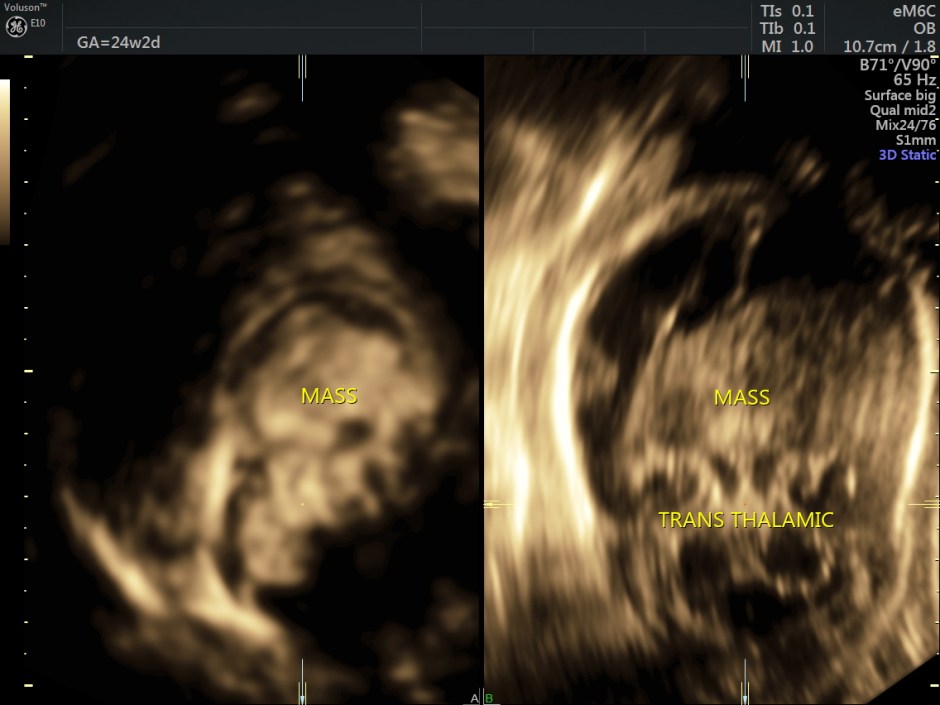

A careful look at the 3rd ventricle shows a solid mass.

Some reconstructed images are given below.

Choroid plexus papilloma (CPP) is a rare and benign tumor composed of epithelial cells that line the ventricular choroid plexus and correspond to 0.4%-0.6% of fetal intracranial tumors. CPP may develop in the lateral ventricle, third ventricle, and fourth ventricle. It is generally diagnosed during the third trimester and is always associated with unilateral or bilateral ventriculomegaly. CPP has slow growth and noninvasive behavior; however, because of its specific location, CPP can block the drainage of cerebrospinal fluid and cause hydrocephalus.

An echogenic mass involving the choroid plexus is visualized on US and MRI. Color Doppler imaging may be useful to show vascularization in the lesion.